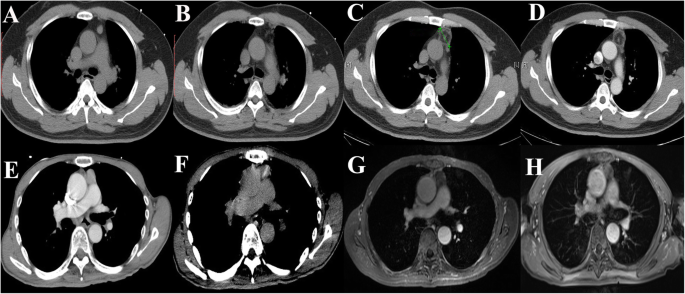

When the procedure started, intravenous anesthesia (remifentanil, 0.05–0.1 μg/kg/min) was administered, and the vital signs of the patient were closely monitored by the anesthetists. After disinfection, a subcutaneous injection of lidocaine was administered at the puncture site. A 17 G probe was inserted step-by-step from the puncture site following the planned puncture pathway (Fig. 2). Repetitive plain scanning followed each step of the insertion during the step-by-step procedure to adjust the probe to the planned pathway. When the probe was placed in the perfect position, the ablation was started. The length of the ablation time was mainly determined by the size of the mass.

Illustration of the step-by-step puncture procedure and appearance immediately after ablation. The size of the thymoma was included to calculate the ablation time before puncture (a). After designing the puncture approach, the step-by-step puncture was performed from the surface to the tumor, as shown (b-i). Immediately after ablation, an additional CT scan was performed to identify residual lesion tissue (j, k and l). The lesion was completely ablated

When the ablation was completed, contrast-enhanced CT scanning was performed to map the residual lesion(s). If the ablated margin surrounding the tumor was < 5 mm, the ablation time was prolonged. After complete ablation was confirmed, coagulation was performed along the needle tract before the probe was removed to prevent metastasis along the tract. After the procedure, an additional CT scan was performed to ensure that there were no signs of bleeding or pneumothorax (Fig. 3).

Follow-ups after ablation. The images in the first row belong to one patient, and the images in the second row are from another patient. a and e are the preoperative images. b and f are images immediately after ablation. c and g are the follow-up images one month later. There was no residual lesion tissue or recurrence. d is the follow-up image three months later. h is the follow-up image one year later. There was no residual lesion tissue or recurrence. Routine follow-up was essential for the early detection of recurrences

All ablations were performed by the radiologist under CT guidance with the 16-slice PHILIPS Brilliance TM Big Bore CT. The average operation time was 52 min (ranging from 41 to 67 min), while the average time for ablation was only 15 min (ranging from 10 to 20 min). Minimum blood loss was involved. The average hospital length of stay was 4 days (ranging from 3 to 6 days). All lesions were completely ablated (13/13, 100%) based on the CT scans that were acquired immediately after RFA (Fig. 2j, k, l). The median follow-up time was 80.5 months (ranging from 64.6 to 116.9 months). Regarding the follow-up appointment observations, only one out of the thirteen patients had recurrence at 35.5 months after the initial ablation (1/13, 7.7%). The patient with recurrence was immediately examined to determine the optimal treatment. The details are shown in Table 2.